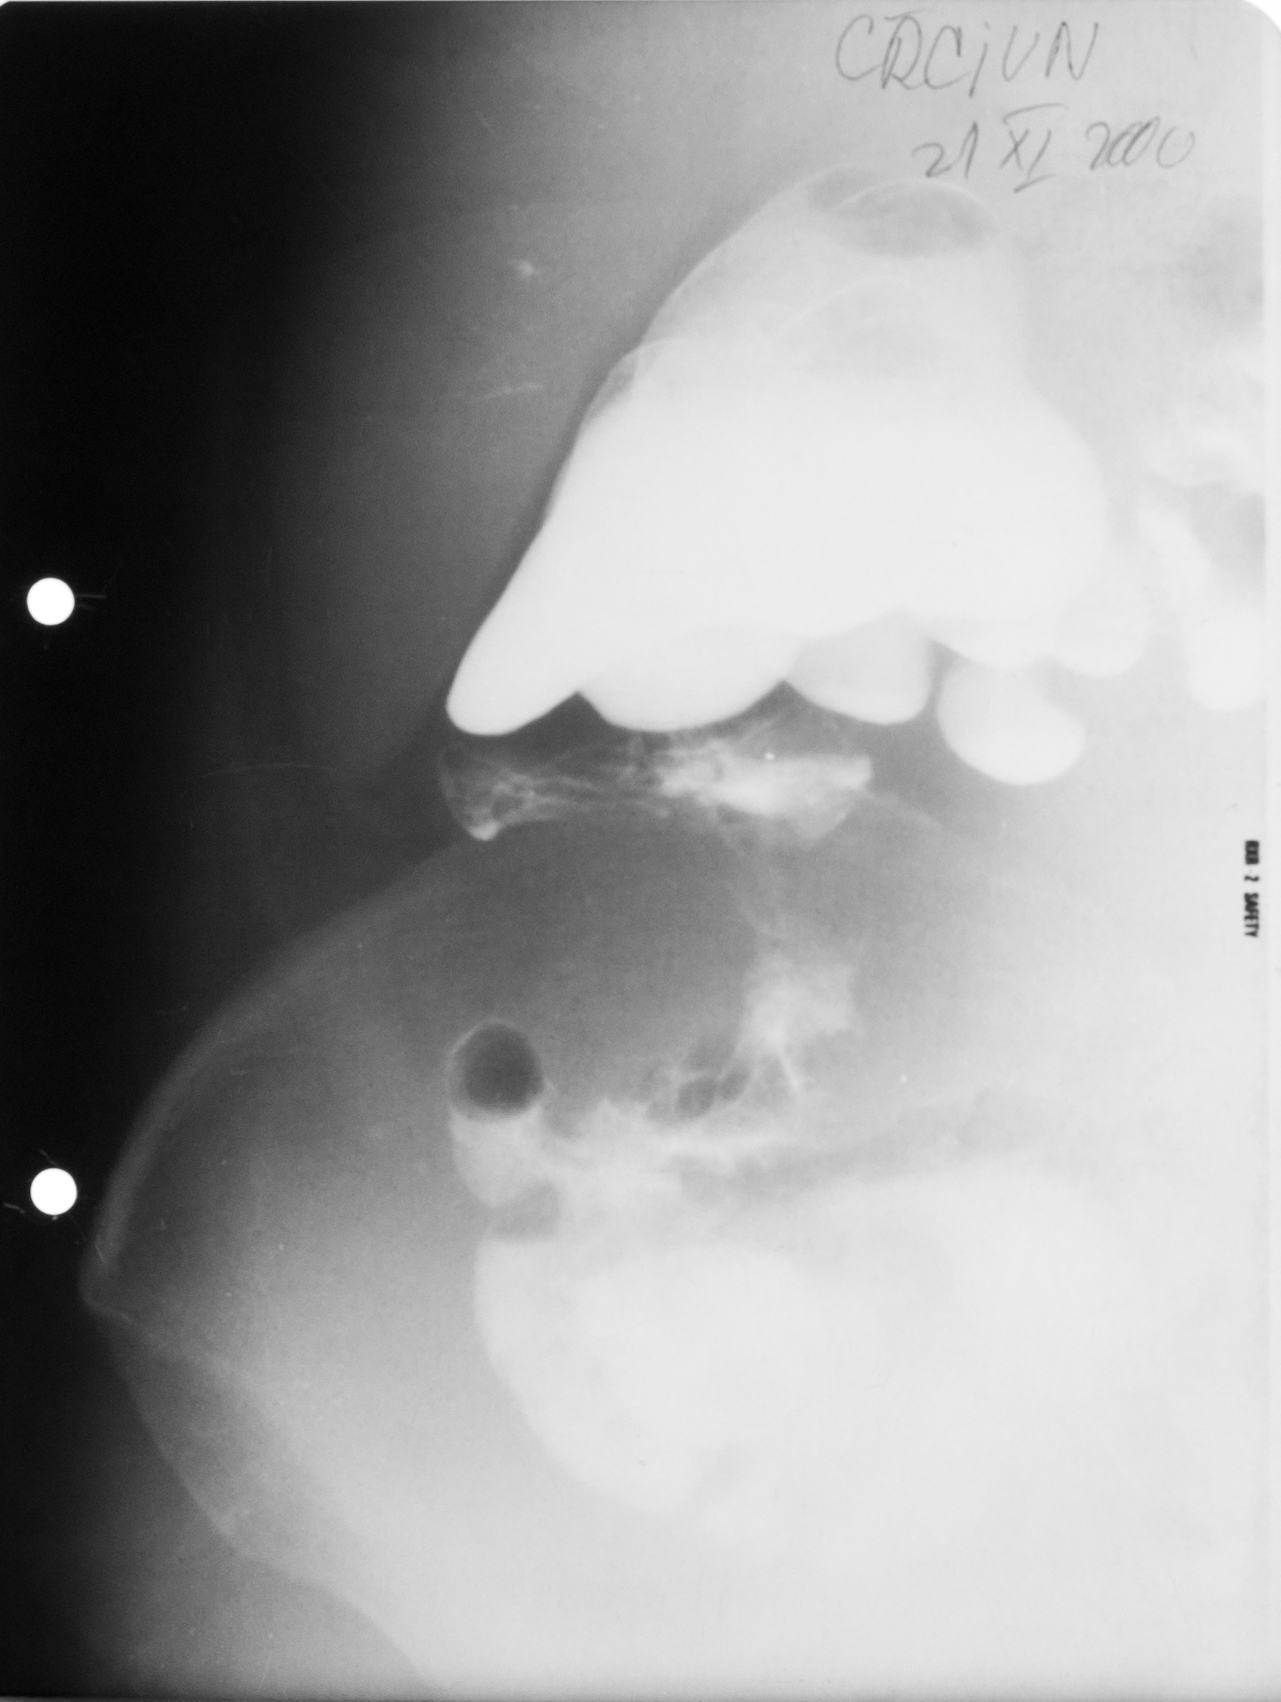

STOMAC NORMOTON(aspectul radiologic)

Tranzitul baritat al stomacului.Aspectul stomacului cu substanță de contrast:forma literei J cu fornix,corp,antru,canal piloric + bulb duodenal,D2(partea descendentă a duodenului

STOMAC ORIENTALIZAT/HIPERTON (aspect radiologic normal)

Stomacul hiperton este caracteristic persoanelor scurte și grase

STOMAC ALUNGIT (aspect radiologic normal)

Stomac alungit cu polul inferior aproape de nivelul crestei iliace.Este caracteristic persoanelor longiline

STOMAC DILATAT

Stomac destins cu substanță de contrast cu polul inferior aflat în micul bazin

Stomac dilatat cu mult lichid de secreție și stază gastrică

: NIȘA BENIGNĂ

Tranzit baritat la nivelul stomacului..La nivelul curburii mici se observă o imagine de adiție mai mult adâncă decât lată,cu pliuri de mucoasă ce converg spre zona respectivă

NIȘĂ BENIGNĂ

Nișă benignă mai mult adâncă decât lată,tot la nivelul micii curburi

ASPECT DE CLEPSIDRĂ AXIALĂ

Tranzit baritat cu aspect biloculat al corpului gastric:aspect de clepsidră axială(ceea ce înseamnă că în zona mediocorporeală se află un neoplasm infiltrativ)

ASPECT BILOCULAT AL CORPULUI GASTRIC

Tranzit baritat la nivelul corpului gastric cu incizură la nivelul curburii mari și aspect biloculat al corpului gastric:biloculare de tip benignă

Biloculare excentrică?

ASPECT BILOCULAT AL CORPULUI GASTRIC

Biloculare excentrică

NIȘĂ BENIGNĂ

Tranzit baritat la nivelul stomacului..Se observă o imagine de adiție,nișă de tip benign,mai mult adâncă decât lată

: NIȘĂ BENIGNĂ

Nișă benignă care iese din conturul gastric,mai mult adâncă decât lată

Prima imagine de la stânga:examinare în dublu contrast

A doua imagine:examinare în mono contrast

: STENOZĂ

Tranzit baritat cu stenozarea lumenului gastric la nivel corporeal și antral

Stenoză,cel mai probabil,de tip malign

NIȘĂ ÎN LACUNĂ

Examen baritat al corpului gastric

Se observă defecte de umplere,adică dislocuirea substanței de contrast de ceva ce se găsește în lumenul stomacului și anume o masa parenchimatoasă cu contur polilobat.

Cel mai probabil este un proces neoplazic vegetativ de dimensiuni mari,care are la nivelul ei și o ulcerație.Imaginea se numește nișă în lacună.

NIȘA MALIGNĂ ÎN REGIUNEA ANTRALĂ

Nișa malignă este mai mult lată decât adâncă și nu iese din conturul corpului gastric.

Ulcerația este în perete,dar nu iese din conturul peretelui gastric.

ULCERAȚIE CRONICĂ

Se observă,în urma tranzitului baritat,bulbul duodenal cu incizuri la nivelul curburilor,având aspect de treflă,caracteristic pentru ulcerațiile cronice

:NEOPLAZIE INFILTRATIVĂ

Tranzit baritat.Se observă o îngustare semnificativă a lumenului la nivel antral,dând aspect de antru amputat.Nu sunt vizibile pliurile de mucoasă,deci este vorba de o neoplazie infiltrativă.

NIȘĂ LA NIVELUL BULBULUI DUODENAL

Tranzit baritat.La nivelul bulbului duodenal se află o pată persistentă de substanță de contrast,captată la nivelul unei nișe

NIȘĂ DE TIP MALIGN

Nișă de tip malign mai mult lată decât adâncă,situate în regiunea antrală cu pliuri de mucoasă ce converg până în craterul nișei

Tranzit baritat.Bulbul duodenal cu o pată ce persistă pe una din fețele bulbului.Avem de a face cu o nișă de dimensiuni mari la nivelul bulbului